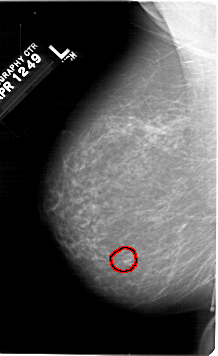

FILE: A_1307_1.LEFT_MLO.OVERLAY

TOTAL_ABNORMALITIES 1

ABNORMALITY 1

LESION_TYPE CALCIFICATION TYPE PLEOMORPHIC DISTRIBUTION CLUSTERED

ASSESSMENT 4

SUBTLETY 4

PATHOLOGY BENIGN

TOTAL_OUTLINES 1

LEFT_MLO LINES 6751 PIXELS_PER_LINE 4126 BITS_PER_PIXEL 12 RESOLUTION 43.5 OVERLAY